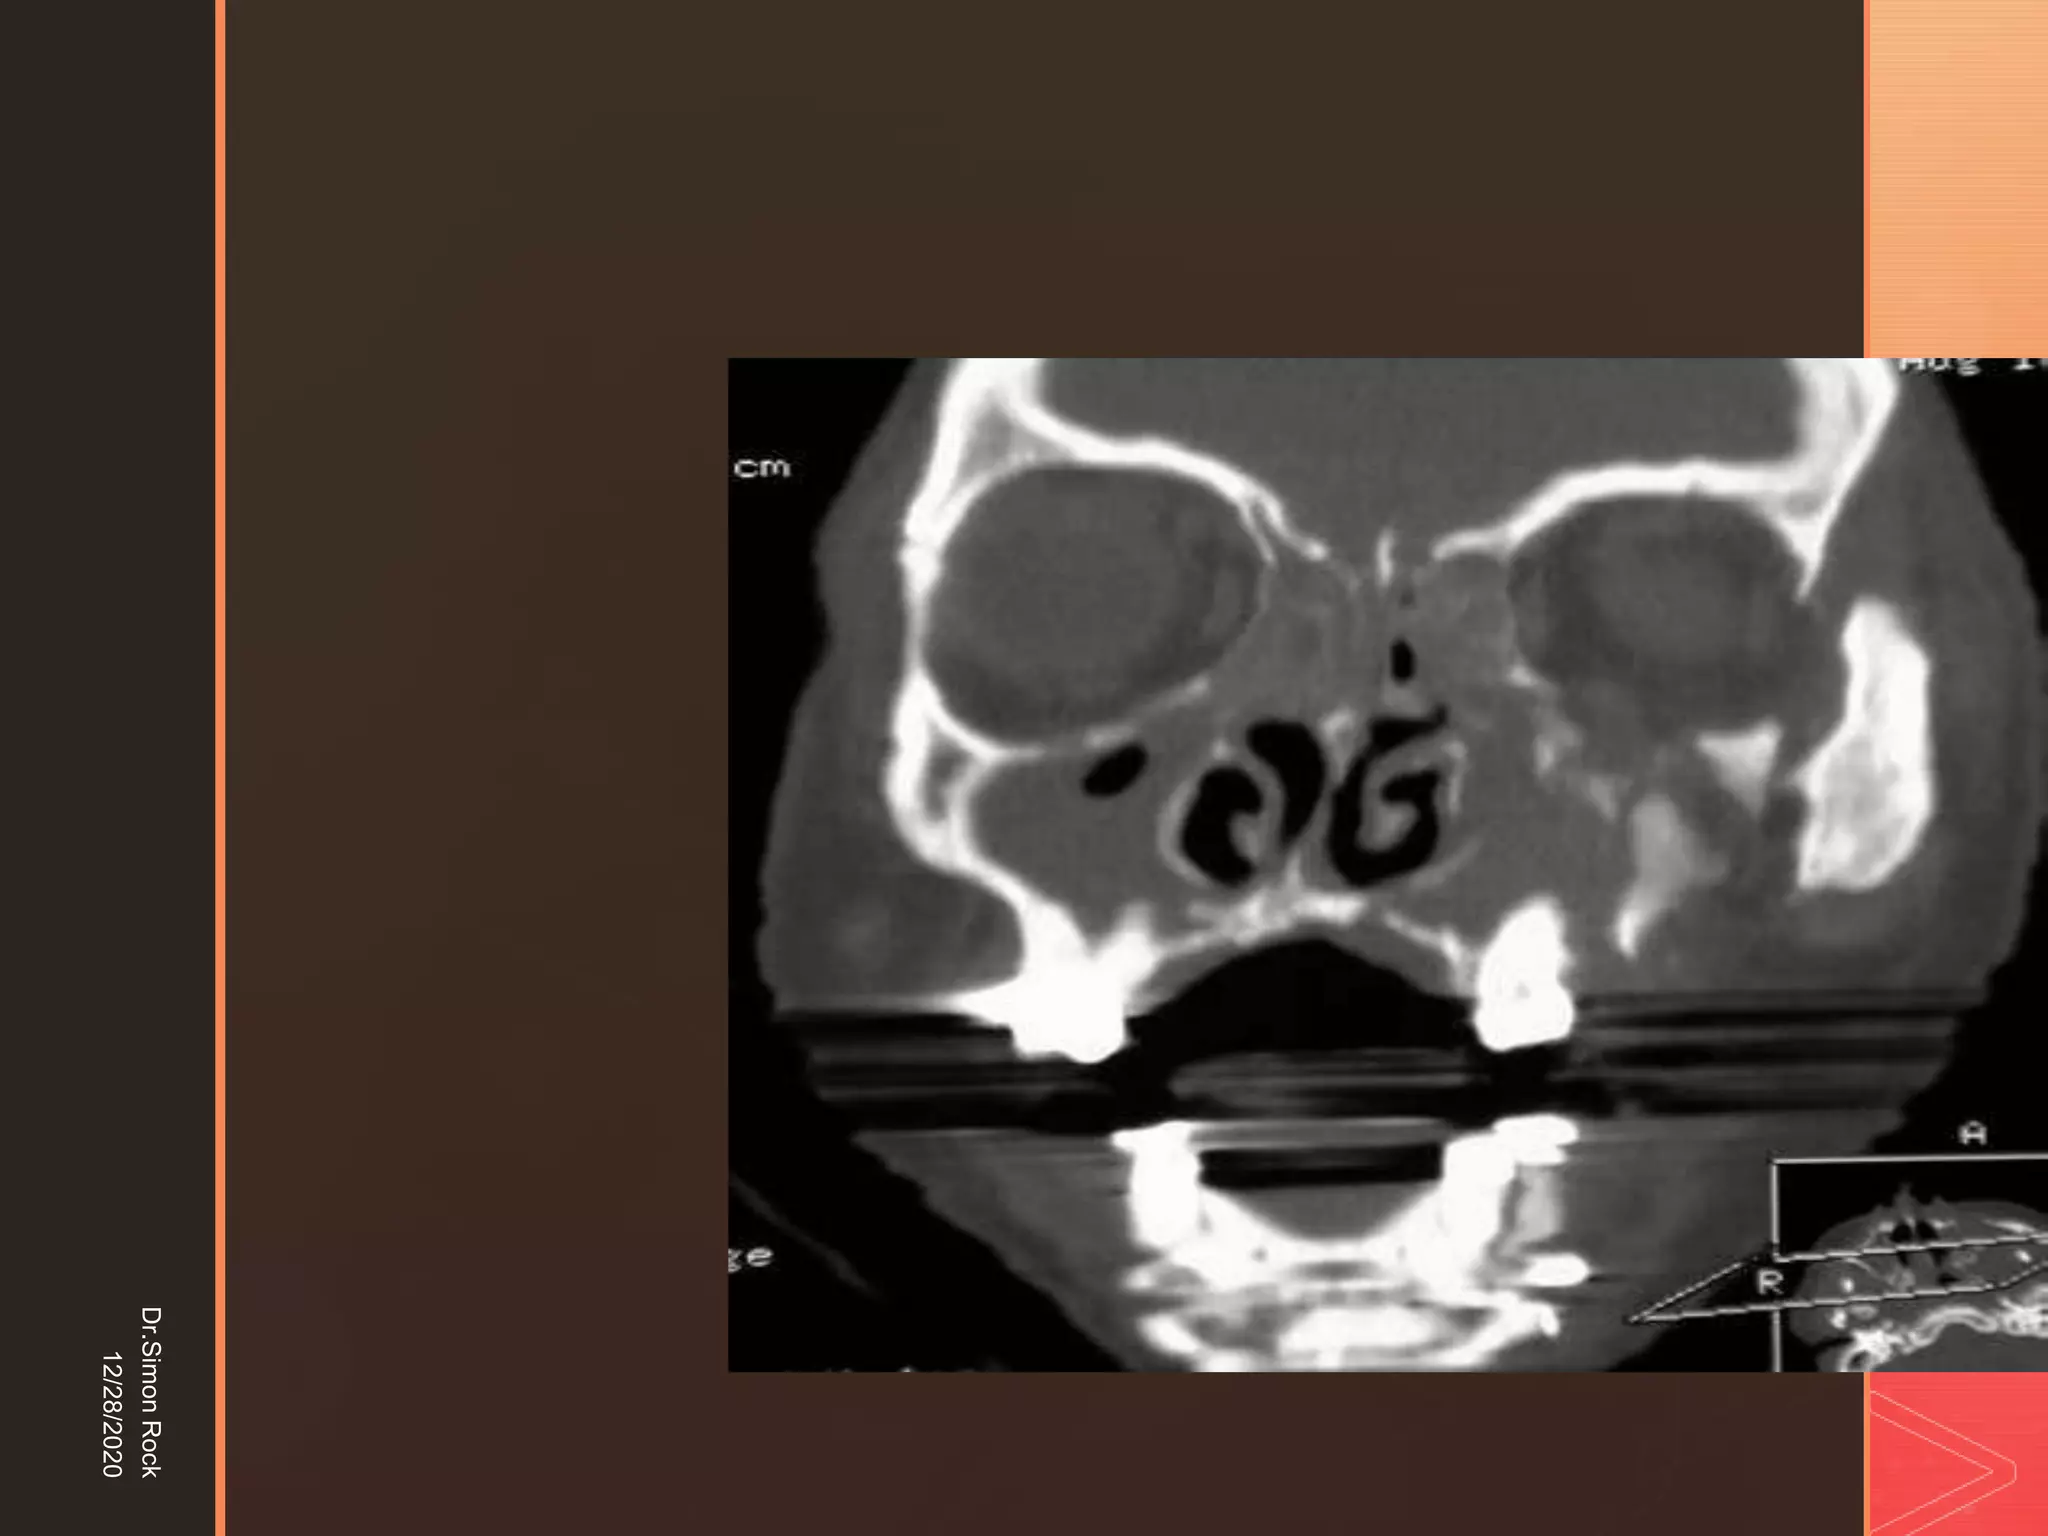

This document discusses the anatomy and fractures of the zygomatic bone. It notes that the zygoma forms the cheekbone and articulates with several other facial bones. Zygomatic fractures most commonly occur in the arch or body due to blunt trauma. Diagnosis involves checking for diplopia, ecchymosis, and other signs of orbital or facial bone involvement. Treatment may involve closed or open reduction based on the severity of displacement. Closed reduction techniques try to elevate the bone back into position without surgery, while open reduction requires surgical exposure and fixation of the fracture site.